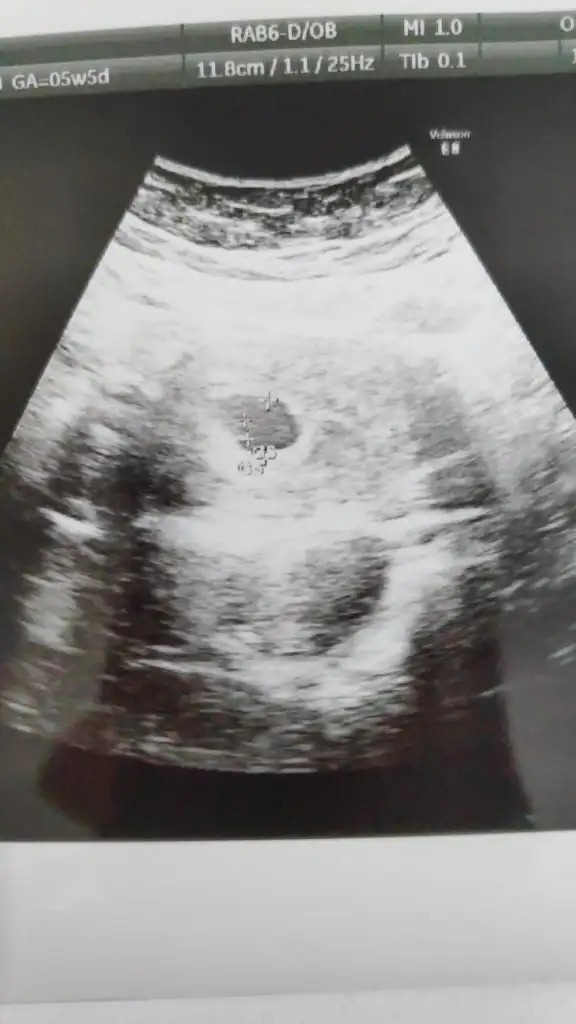

Ben de çin takvimide tuttu ona baktınmıAttım ama doktordayken daha net gözüküyordu sol alttaydı yolk![]()

Kız valla ultrason fotosundan iyi görüyorsunuz ben doktor ekranda gösterdiğinde net gördüm yolk falan çıktı verince kağıtta bir şey göremedimBenimkide soldaydı plesanta da soldaydı. Ramzi teorisi çok nadir yanılıyor canım ya. Benimde çin takvimi işe yaramadı çünkü öyle bi zamandı ki bigün sonra erkek bi gün sonra kız dıbende Ramzi teorisini baya ilerlettim o yüzden

Yorumlarız tabi canım ama fazla büyümemesi gerek büyüdükçe ortalıyor yerini çünküKızlar benide yorumlarsınız değilmi ultrason kağıdımı alınca

Tabiki burda paylaşırsın bakarızKızlar benide yorumlarsınız değilmi ultrason kağıdımı alınca

Net bişey diyemeyiz kuzum ama solda olunca erkek oluyormuş bak ramzi teorisi diye araştır. Karından ultrasondu dimiKız valla ultrason fotosundan iyi görüyorsunuz ben doktor ekranda gösterdiğinde net gördüm yolk falan çıktı verince kağıtta bir şey göremedim

Bana erkek dedin erkek çıktı valla canımNet bişey diyemeyiz kuzum ama solda olunca erkek oluyormuş bak ramzi teorisi diye araştır. Karından ultrasondu dimi![]()

Evet karındanNet bişey diyemeyiz kuzum ama solda olunca erkek oluyormuş bak ramzi teorisi diye araştır. Karından ultrasondu dimi![]()

Hayırlısı olsun inşallahErkek canım evetben hemen gördüm belli oluyor aslında. Zaten işaretlemişte